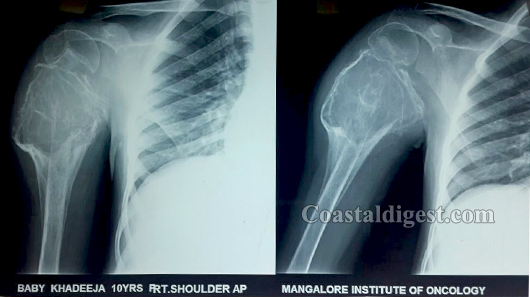

Mangaluru, Mar 3: A complex and rare surgery was performed at city based Unity Health Complex by Dr Jalaluddin Akbar to save the arm of a 10 year-old-girl who was suffering from cancer of the right arm bone, presented to Mangalore Institute of Oncology.

The procedure was to remove the bone and joint of the right arm and reconstructed by taking one of the bone from leg of the patient. The surgery took 12 hours & was performed successfully for the first time in this region.